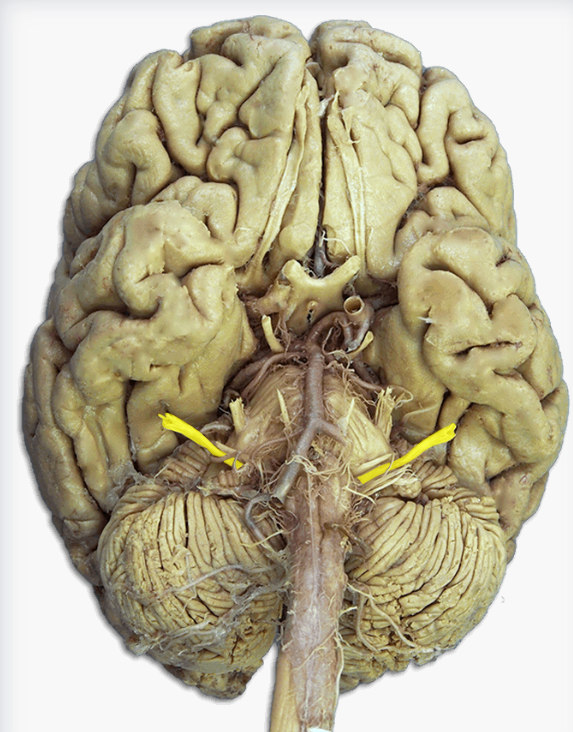

Label this cranial nerve

Olfactory (CN I) nerve

Label this cranial nerve

Optic (CN II) nerve

Label this cranial nerve

Oculomotor (CN III) nerve

Label this cranial nerve

Trochlear (CN IV) nerve

Label this cranial nerve

Trigeminal (CN V) nerve

Label this cranial nerve

Abducens (CN VI) nerve

Label this cranial nerve

Facial (CN VII) nerve

Label this cranial nerve

Vestibulocochlear (VIII) nerve

Label this cranial nerve

Glossopharyngeal (CN IX) nerve

Label this cranial nerve

Vagus (CN X) nerve

Label this cranial nerve

Accessory (CN XI) nerve

Label this cranial nerve

Hypoglossal (CN XII) nerve